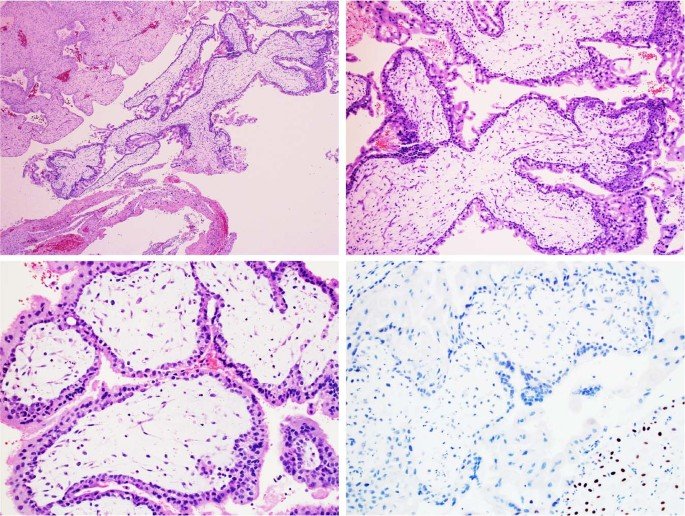

Gestational trophoblastic disease (GTD) is the term given to a group of rare tumors that develop during the early stages of pregnancy. After conception, a woman’s body prepares for pregnancy by surrounding the newly fertilized egg or embryo with a layer of cells called the trophoblast. The trophoblast helps the embryo implant itself to the uterine wall. These cells also form a large part of the tissue that make up the placenta — the organ that supplies nutrients to a developing fetus. In GTD, there are abnormal changes in the trophoblast cells that cause tumors to develop.

Choriocarcinoma: This cancerous tumor forms inside a pregnant woman’s uterus. Choriocarcinomas usually occur when growths from molar pregnancies turn cancerous. Rarely, choriocarcinomas form from tissue left in the uterus after a miscarriage, an abortion or the delivery of a healthy baby.